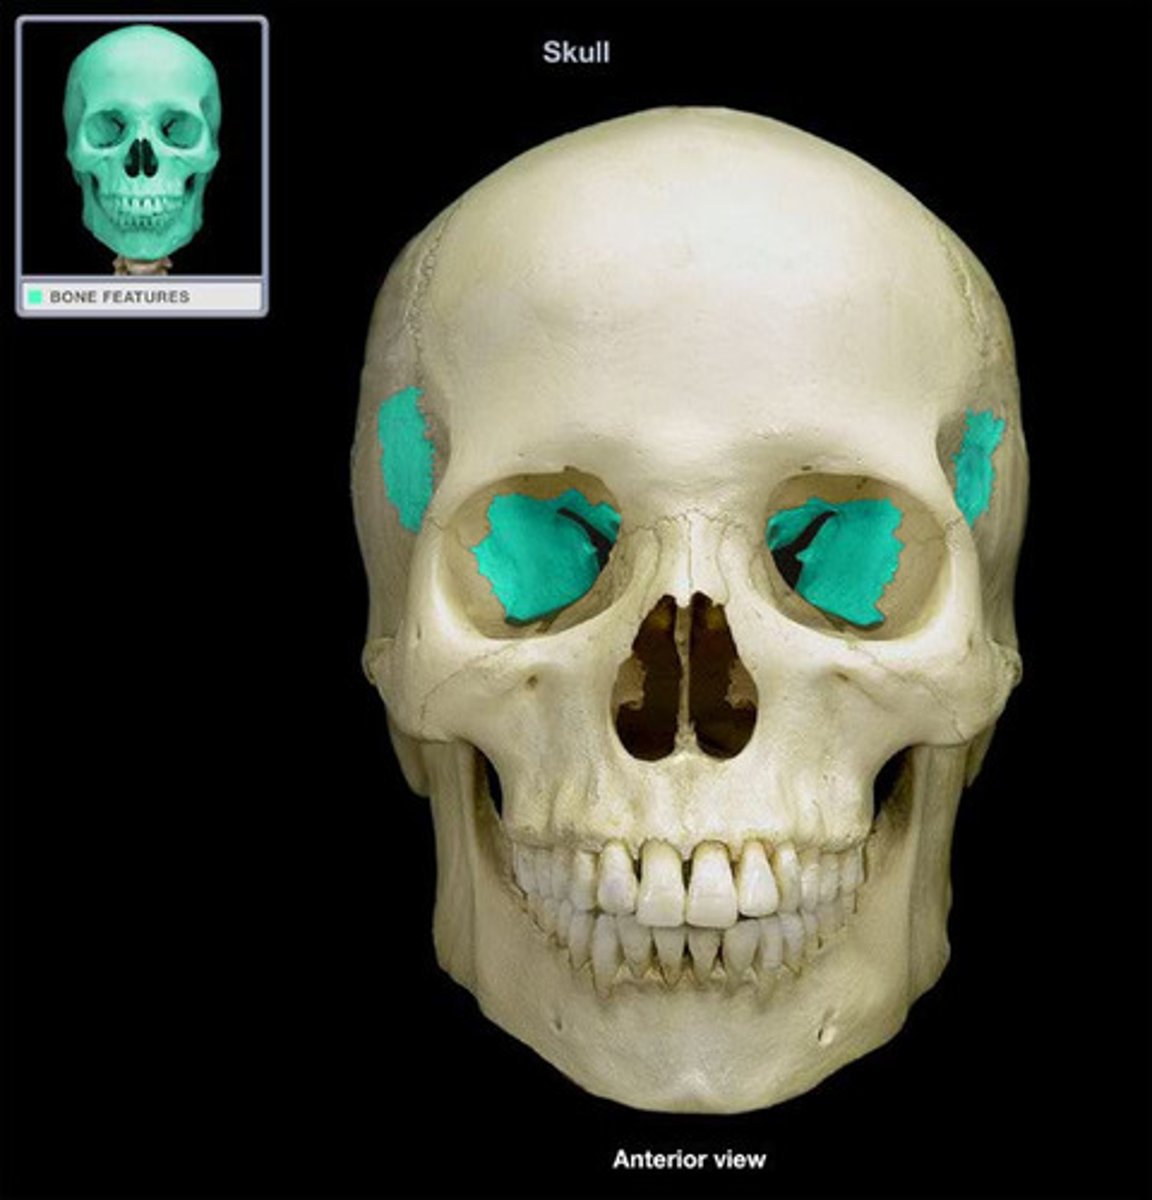

greater wings

Name this structure.

lesser wings

Name this structure.

superior orbital fissure

Name this structure.

inferior orbital fissure

Name this structure.

optic canal

Name this structure.